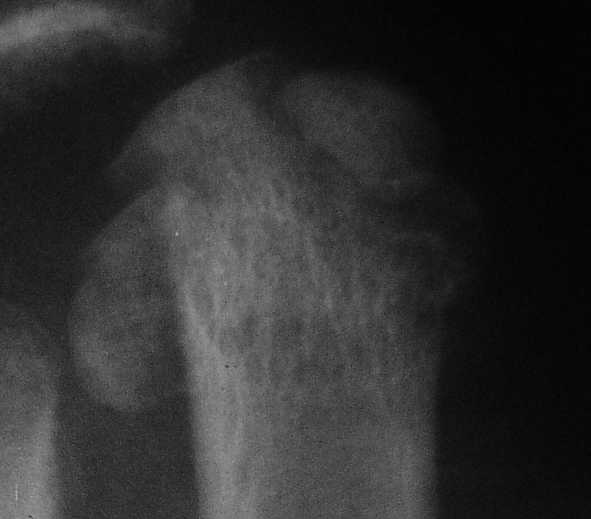

1 передний отдел стопы делается в косой, а не боковой проекции - на боковой все плюсневые кости накладываются друг на друга, и ничего не видно - это же аксиоматично! Я, например, на прямых проекциях не вижу совсем признаков перелома первой и четвертой плюсневой, и сомневаюсь в переломе третьей, боковые же совершенно неинформативны.

Как же суть проблемы видна? Человек говорит о переломе первой (то есть речь идет о переломо-вывихе?), второй, третьей и четвертой плюсневых костей, а я вижу только перелом второй. мне кажется, что проблема в таком случае будет чуть-чуть другая. Кстати, сколько переломов насчитали на этих снимках Вы?

Однозначно-переломы 1,2,3,4 плюсневых костей.

Не знаю, что за проблема, но я на своем мониторе переломы отлично вижу.

Та же проблема - по крайней мере на снимке в аппарате (фас) отчетливо видно перелом ее головки.